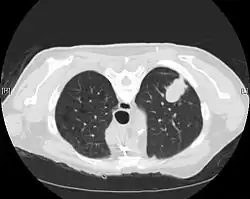

CT scan- adenocarcinoma of the left lung

The majority of lung cancers can be characterized as either small cell lung cancer (SCLC) or non-small cell lung cancer (NSCLC). Lung adenocarcinoma is one of the three major subtypes of NSCLC, which also include squamous carcinoma and large cell carcinoma.[15]

Imaging

CT imaging provides better evaluation of the lungs, with higher sensitivity and specificity for lung cancer compared to chest radiograph (although still significant false positive rate[27]). Computed tomography (CT) that is specifically aimed at evaluating lung cancer includes the chest and the upper abdomen. This allows for evaluation of other relevant anatomic structures such as nearby lymph nodes, adrenal glands, liver, and bones which may show evidence of metastatic spread of disease.[4] Indeed, the US Preventative Services Task Force recommends annual screening with low-dose CT in adults aged 55 to 80 years who have a 30 pack-year smoking history and currently smoke or have quit within the past 15 years, with certain caveats (see Lung cancer screening).[28]